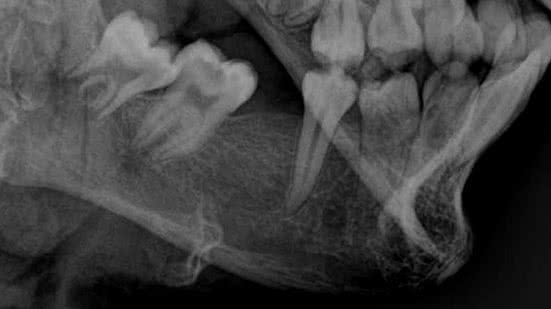

O perito odontolegista João Alfredo Guimarães, responsável pelo exame, explicou que o corpo foi escaneado e as imagens produzidas da arcada dentária foram utilizadas para analisar e comparar com a ficha dentária e as fotos da vítima. Também foi possível fazer a estimativa da idade do corpo, através da cronologia da formação dos dentes, e analisar alguns detalhes da arcada, como a posição dos dentes frontais e a extração de um dente que constava na ficha odontológica.

“Durante o exame odontolegal no corpo do cadáver identificamos várias evidências como idade estimada, ausência dentária e posição dentária compatíveis com aqueles encontrados na certidão de nascimento, documentação odontológica e fotos pertencentes a vítima. Todos esses achados periciais permitiram concluir que se trata da mesma pessoa, ou seja, a vítima realmente era o adolescente Mateus Lima”, afirmou o odontolegista.